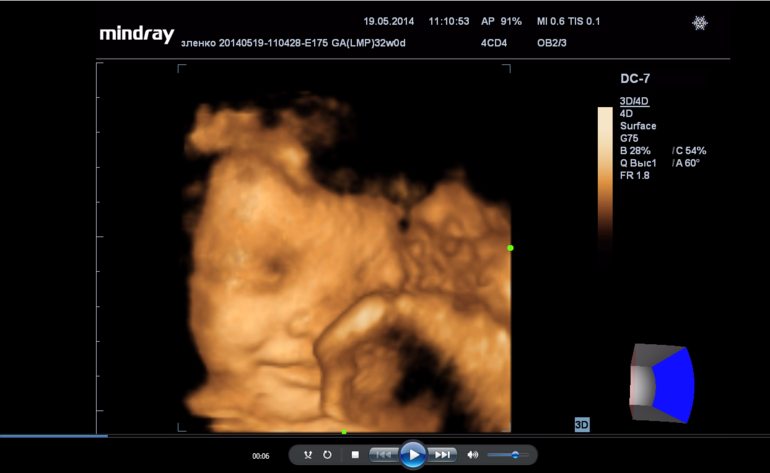

3D УЗИ (третий триместр)

делала в 24,хорошо все видно было, во второй раз в 32,уже дочка слишком большая была.

на 24-25 неделе делала)) очень крутые ощущения были) хорошо видно лицо,ребенок улыбался и показывал язык)) в 3м триместре уже большой ребенок можно не увидеть хотя точно не уверенна..